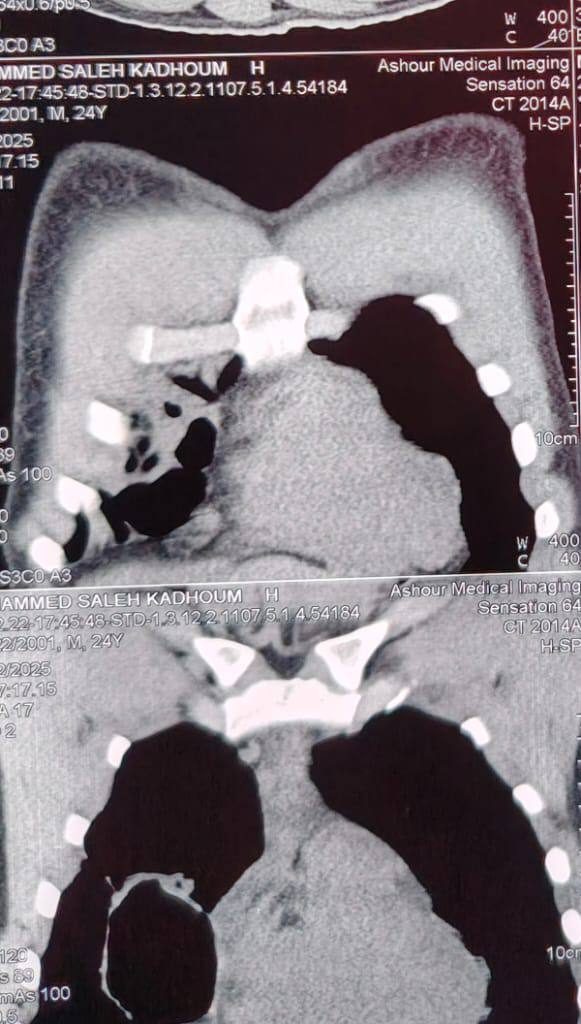

الشاب، وهو من محافظة بغداد، كان قد خضع في وقت سابق لتدخل جراحي غير ناجح في أحد المراكز الصحية، ما أدى إلى تدهور حالته الصحية بشكل كبير ودخولها مرحلة حرجة، تمثلت بوجود نواسير قصبية متعددة ومفتوحة على تجويف الصدر، مع تجمع سوائل والتهابات مزمنة، إضافة إلى ارتباط الكيس بالقصبة الهوائية وحدوث تليفات شديدة في أنسجة الرئة، الأمر الذي دفع عدة مراكز طبية إلى الاعتذار عن استقباله نظرًا لخطورة وتعقيد الحالة.

العملية الجراحية، التي استغرقت أكثر من ثلاث ساعات من العمل الدقيق، تضمنت تقشيرًا كاملًا للرئة ورفع التليفات الشديدة، مع إزالة بقايا الكيس المائي المفجور، وإغلاق النواسير الهوائية المتعددة بدقة متناهية، وذلك دون استئصال أي جزء من الرئة، مع الحفاظ الكامل على الوظيفة التنفسية للمريض.